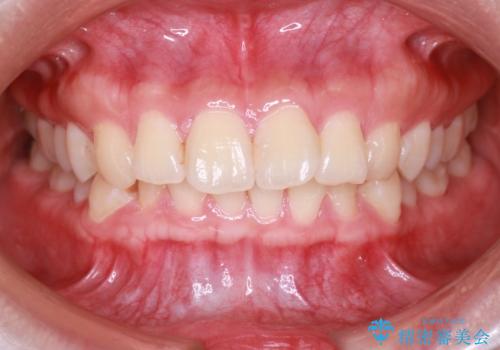

【インビザライン】翼状捻転+出っ歯を治したい

- 前歯の捻れと口元の突出を主訴に来院されました。

インビザラインを用いて上顎の遠心移動を行い、前歯を下げながら凸凹を綺麗に治すことができました。